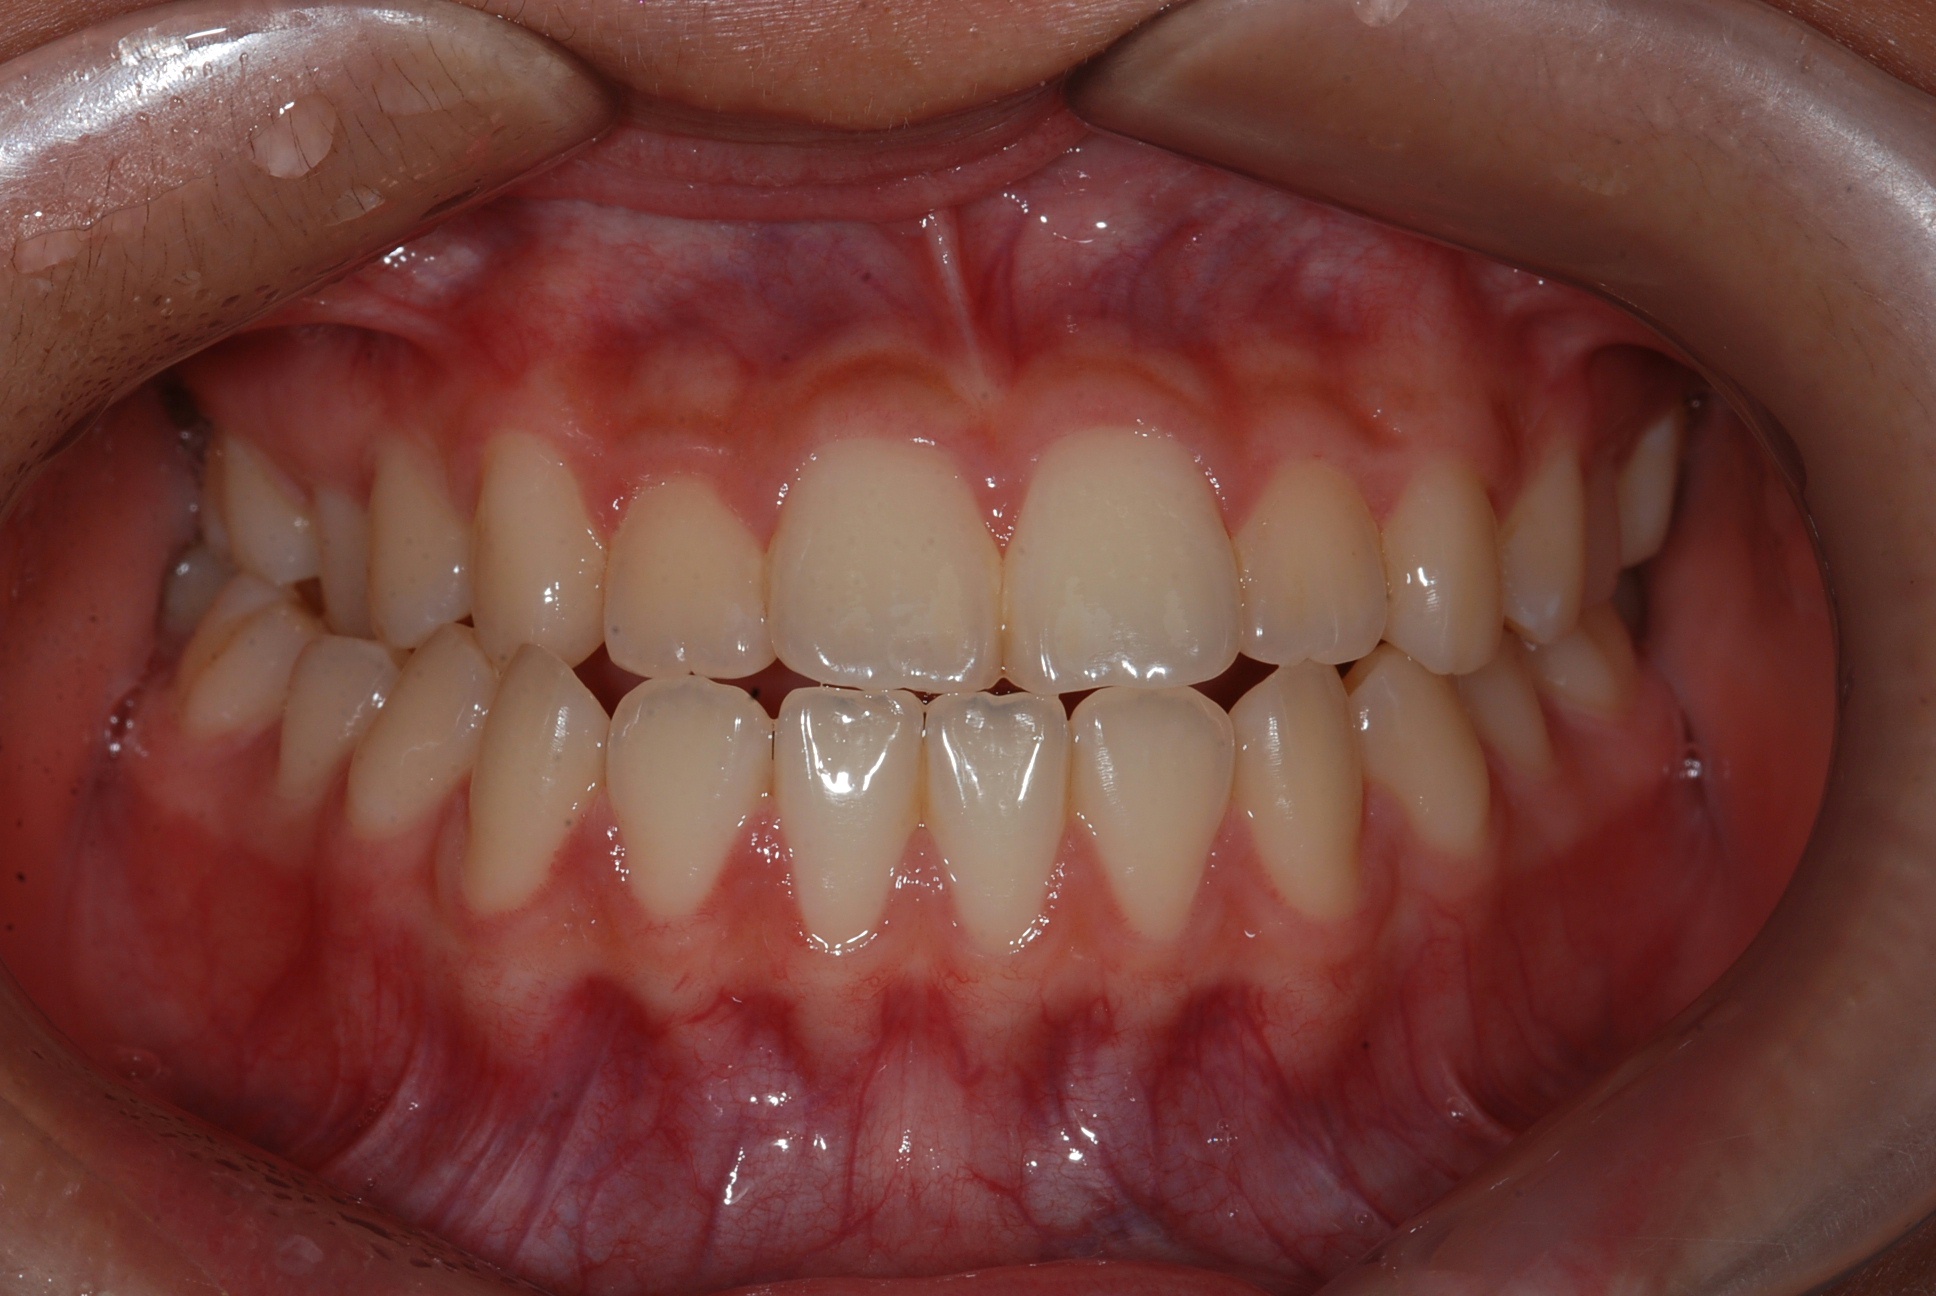

치료 후 사진입니다.